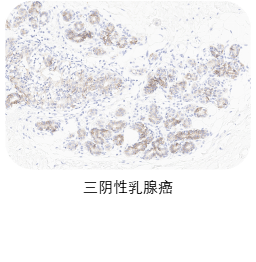

❷ 适应症癌种染色

选取肿瘤组织样本用于敏感性染色,TROP2一抗染色阳性细胞细胞质和/或细胞膜特异性阳性着色(染色强度≥1),无非特异性着色(染色强度<1),无背景染色(染色强度<1 )。

ACRO IHC实验室目前已建立了成熟的TROP2染色方法与判读体系,适用三阴性乳腺癌、前列腺癌、胰腺癌、卵巢癌、皮肤癌等多个癌种,可快速用于相关肿瘤的临床试验入组筛选与样本检测,部分结果展示如图所示。